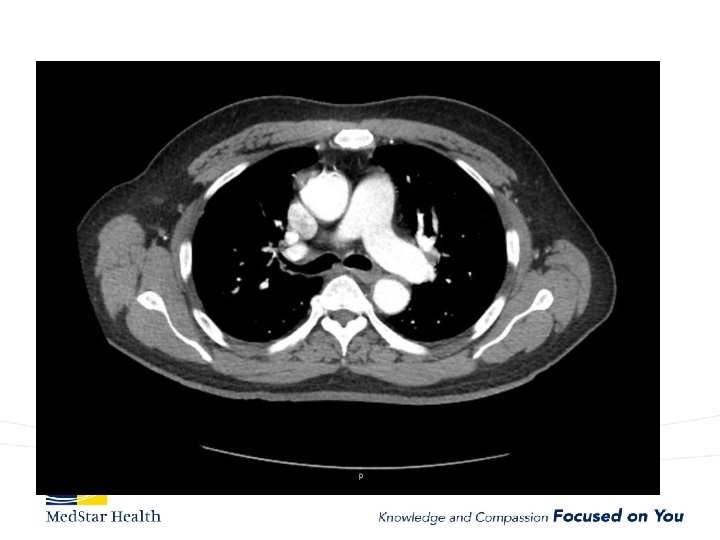

Acute Type B Aortic Dissection • Incidence: 2. 6 -3. 5 per 100, 000 patient-year • Uncomplicated • Complicated – – Malperfusion Rupture Unremitting Pain Uncontrolled HTN

How Do We Treat • Open repair-unacceptable morbidity and mortality • TEVAR – Improved morbidity and mortality – Coverage of primary entry tear – Additional coverage?

Type B Dissection Complicated Uncomplicated Risk TEVAR age, comorbidities Extreme Low Medical Management False Lumen Small, Thrombosed Medical Management Patent/Large(>22 mm), Total Aorta >40 mm TEVAR/adjuncts